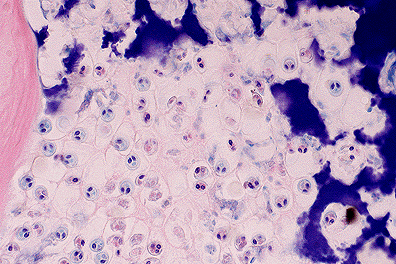

M. cerebralis trophozoites within the cartilage of the head in a rainbow trout. Note the characteristic two prominent polar bodies within each parasite. (40X, HE, 97K)

Laboratory Results: Enzymatic digests performed on head samples showed numerous, approximately 20 æm diameter, acid-fast, spherical spores containing 2 piriform polar bodies and an ovoid sporoplasm, consistent with M. cerebralis.

Contributor's Diagnosis and Comments: Chondritis, granulomatous, multifocal, moderate, chronic, with intralesional myxosporidian trophozoites and spores, consistent with Myxobolus cerebralis.

Granulomatous chondritis with intralesional trophozoites and mature spores are common in juvenile fish infected with M. cerebralis. In older fish, islands of retained, hyperbasophilic cartilage with entrapped spores are within bone; associated inflammation is rare.

The life cycle of M. cerebralis involves a tubificid oligochaete in which numerous motile actinospores (Triactinomyxon gyrosalmo) are produced.2 Actinospores are ingested by trout or directly penetrate the mucous membranes and migrate to bone and cartilage. Asexual reproduction results in numerous trophozoites followed by spore formation within cartilage.3